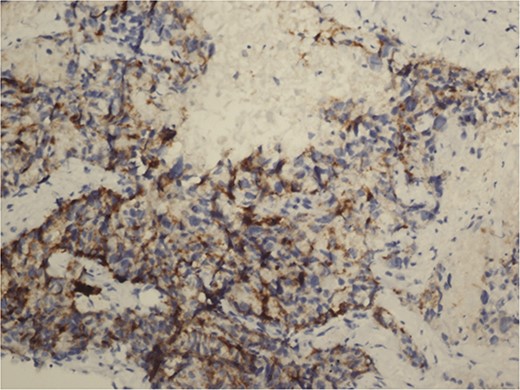

A 59-year-old woman presented with complaints of abdominal pain and abdominal distension for about a month. There was no known systemic disease and no history of previous abdominal surgery. It was learned that the patient had been admitted to the emergency department in another center one month ago with the current complaints and was discharged after medical treatment. Physical examination at the time of admission revealed abdominal distension and diffuse minimal tenderness with no signs of peritoneal irritation. Laboratory tests revealed that hemogram and biochemical parameters were within normal limits, but one of the tumor markers, the patient’s CA 19-9 level was significantly elevated at 855 U/ml (normal range: 0–37 U/ml). Contrast-enhanced CT scan showed a 10×10 cm heterogeneous mass in liver segments 4B-5, extending to segment 6, and free fluid adjacent to the liver and irregular liver contours. Borders of the gallbladder could not be seen. Soft tissues forming nodular mass formation were detected on the omental surfaces (Fig. 1). Computed tomography examination performed at the center where the patient was admitted as an emergency one month ago revealed hypodense lesions measuring 10×8 cm in size in the left lobe of the liver, protruding into the inferior perihepatic area, and 3.5 cm in diameter in segment 5 of the right lobe with no significant contrast enhancement after intravenous injection of contrast material. Perihepatic ascites was not detected and gallbladder size, wall thickness and lumen were normal (Fig. 2). In the light of the radiologic findings, a pre-diagnosis of progressive gallbladder malignancy was considered. The patient was hospitalized in the General Surgery ward for further investigation and treatment. Because of the presence of ascites causing abdominal distension, a percutaneous ascites drainage catheter was placed and 5000 cc ascites drainage was performed. Cytologic examination of the ascitic fluid revealed cell groups with unclear three-dimensional cytonuclear detail among lymphocytes and mesothelial cells with reactive atypia and malignancy was considered suspicious. With the current radiologic and cytologic findings, inoperable metastatic gallbladder carcinoma was considered. Medical treatment was decided by the multidisciplinary oncology council and 18G needle tru-cut biopsy was performed from the 10×10 cm mass adjacent to the gallbladder for definitive tissue diagnosis and adjuvant treatment planning. Histopathologic examination revealed a diagnosis of neuroendocrine carcinoma (NEC) (Fig. 3). Immunohistochemical examination revealed strong staining of tumor cells with CD56 (Fig. 4), synaptophysin (Fig. 5), chromogranin A (Fig. 6), and Ki67 index was >90% (Fig. 7). Weak staining was observed with CK19, CK7, and CDx2, but no staining was observed with CEA and CK20. Morphologic findings were compatible with small cell type. Etoposide and cisplatin chemotherapy was planned but the patient’s general condition deteriorated progressively. The patient couldn’t start chemotherapy and unfortunately resulted in mortality on the 20th day of hospitalization.

The diagnosis of small cell NEC typically involves a combination of clinical evaluation, imaging studies, and histopathological examination. Immunohistochemical staining is crucial for confirming neuroendocrine differentiation, with common markers including synaptophysin, chromogranin A, and CD56. A high Ki-67 index is indicative of the aggressive nature of small cell NEC [2].